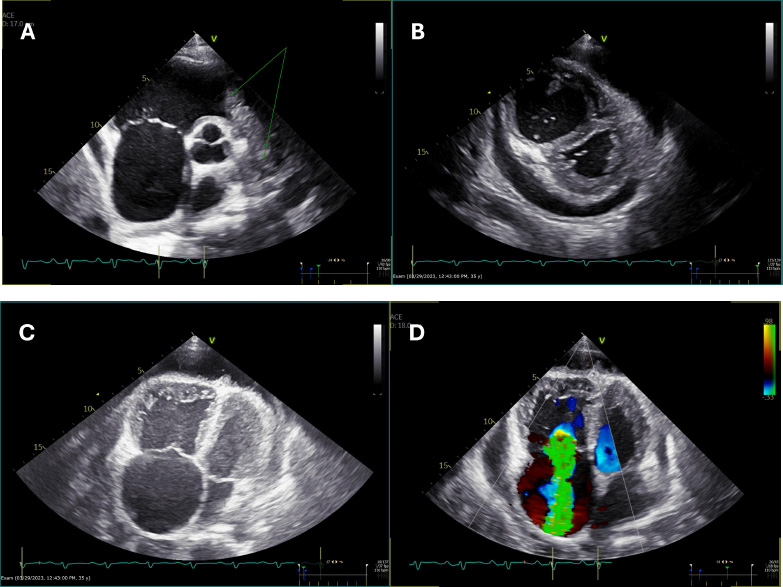

[Electronic Publication Date: August 12, 2025]Ayishath Muhseena, Mohammad Swalih, Treesa P. Varghese and Sharad Chand